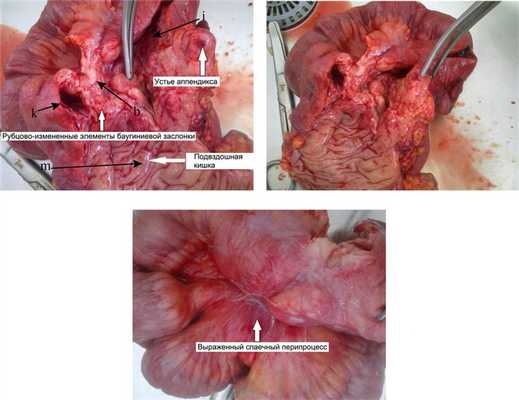

Выполнена лапаротомия, правосторонняя гемиколэктомия с формированием илеотрансверзоанастомоза бок в бок.

Макропрепарат илеоцекальной области представлял собой конгломерат (рис. 3), Рис. 3. Больная Ч., 34 года. Макропрепараты илеоцекального перехода после правосторонней гемиколэктомии. Фото. b — язва; k — просвет восходящей ободочной кишки; i — просвет слепой кишки; m — просвет подвздошной кишки. состоящий из спаянных между собой петель восходящей ободочной, слепой и подвздошной кишок. При рассечении этого участка определялась значительная плотность ткани, деформация стенки, элементы баугиниевой заслонки не дифференцировались, в районе предполагаемой нижней губы баугиниевой заслонки — глубокая язва, неправильной формы, с плотными краями.